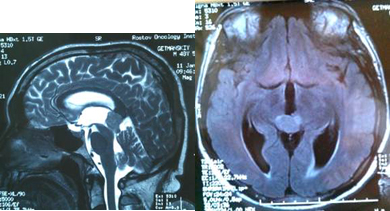

Вентрикуло-перитонеальный шунт: Показания и применение